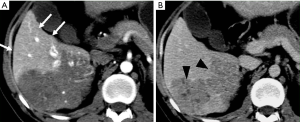

Early enhancement of the portal vein

This is a direct demonstration of a HAPS, usually due to a high-flow arterial fistula, generally a macroscopic arterioportal fistula, transvasal or transtumoral shunt. Two practical findings make this observation easier to diagnose: (I) early main portal vein enhancement, occurring before either the splenic (SV) or superior mesenteric vein (SMV); or (II) early enhancement of peripheral portal vein branches before the common portal vein (Figure 2). Frequently early enhancement will also demonstrate early venous opacification, which can be temporally close to the timing and intensity of the abdominal aorta in the setting of a large shunt.